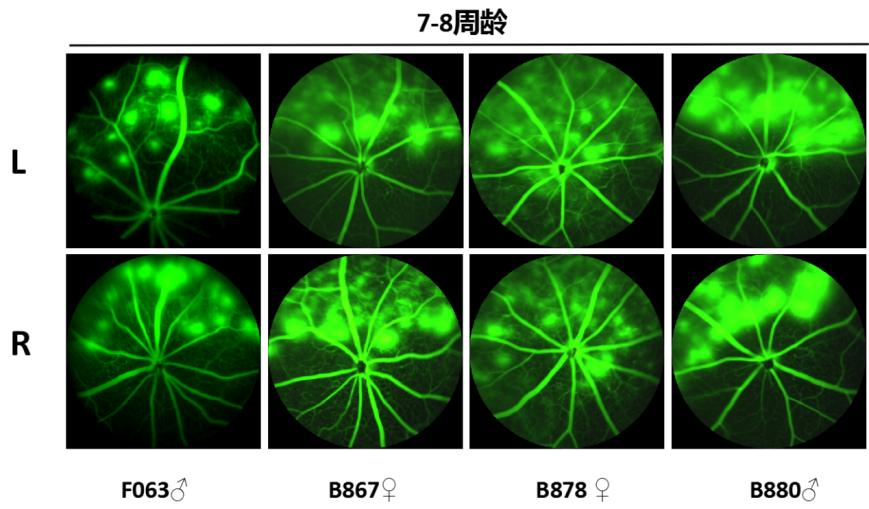

经赛业生物技术团队的实验验证,该hVEGF小鼠的F0代眼底荧光泄露斑块明显、清晰和稳定,与新生血管性黄斑变性疾病表型相似,F1和F2代小鼠均能够稳定遗传亲代表型,适合用于抗VEGFA药效评价等临床前研究中。

FFA(眼底荧光血管造影)结果显示:小鼠眼底出现血管病变,大面积荧光素钠渗漏。

hVEGF小鼠(F0)眼底荧光血管造影结果